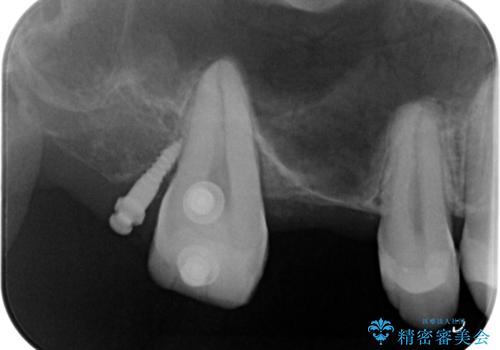

なので親知らずを抜歯して、一番奥の歯を部分矯正(upライト)をして倒れ込んでいる歯を起こしてスペースを作り、ブリッジの治療を行いました。

適合の良いブリッジが入りました。

歯の傾きを改善することにより食べ物が詰まりにくくなりました。

白い被せ物が入り、満足して頂けました。